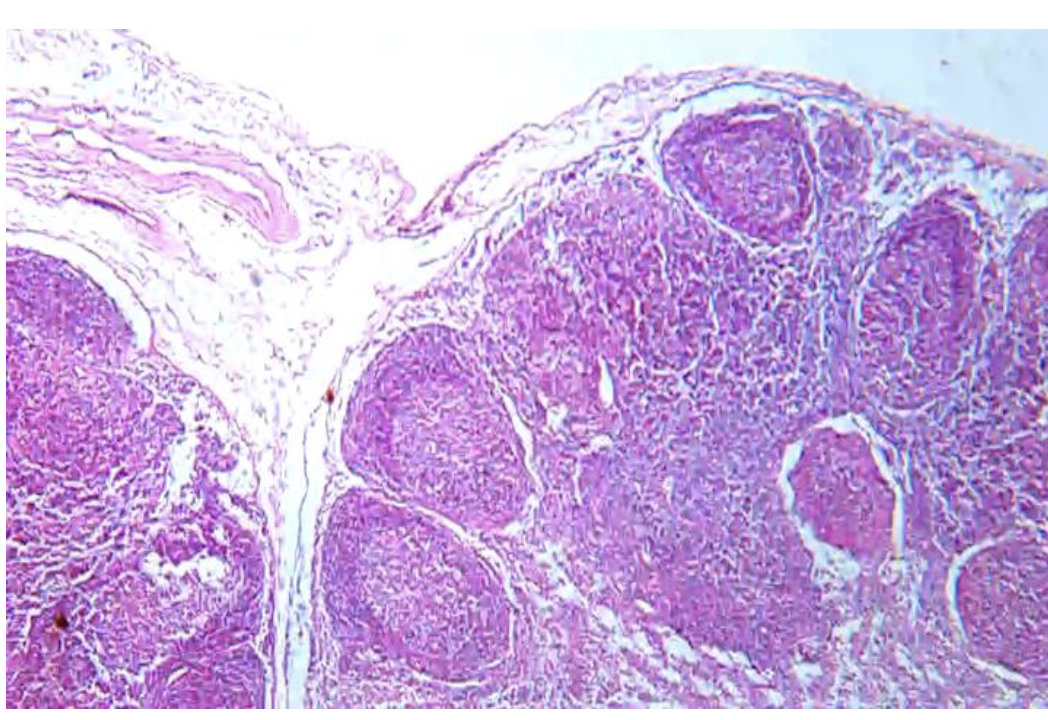

palatine tonsil

A? B? C ?

A___tonsillar crypts

B___non keratinized stratified sq epith

C___lymphatic follicles

اقلب